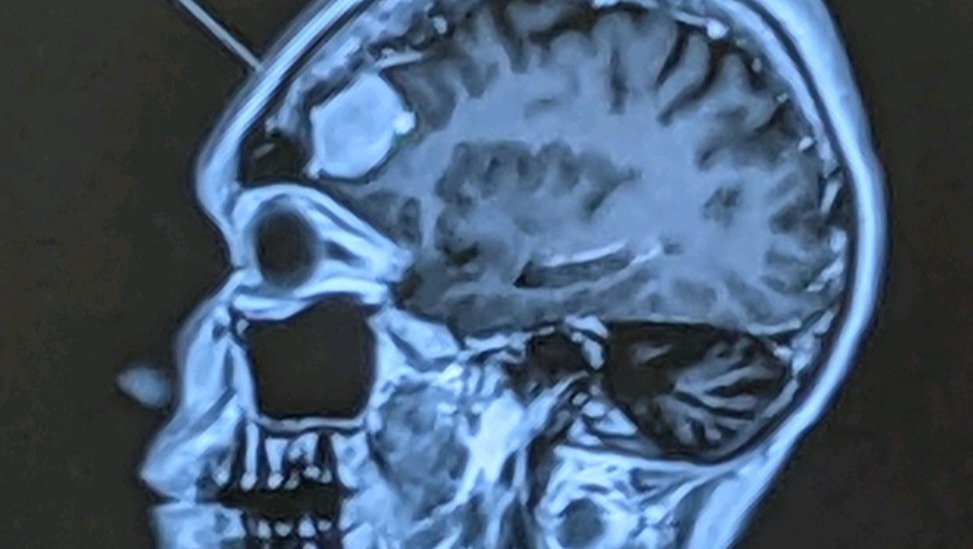

To the date, 17 years later, on September 9th, I got an MRI to see if a concussion I had sustained during a stampede on the 4th of July where I was trampled by a crowd who believed there was an active shooter. My life was once again turned upside down.

The MRI came back with a disturbing image. There it was, a walnut-size tumor right above my left eye.